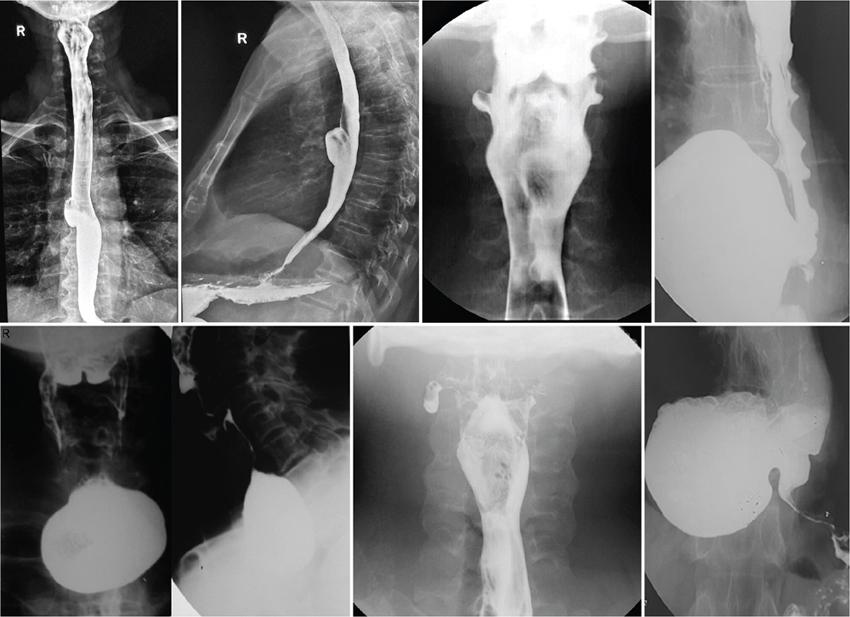

Barium swallow (13 mm tablet/marshmallow/bread soaked in barium) with video fluoroscopy

Inexpensive, easily available

Appropriateness limited on use of spot images and by proficiency/experience of technician/doctor

Can be tailored depending on patient presentation

Negative barium study does not rule out need of endoscopy

Video-fluoroscopy allows adequate/physiological assessment of oesophageal motility

No cross-sectional information obtained

Barium is not absorbed and hence allergic reactions are rare

Barium can elicit severe mediastinitis when used in oesophageal perforations